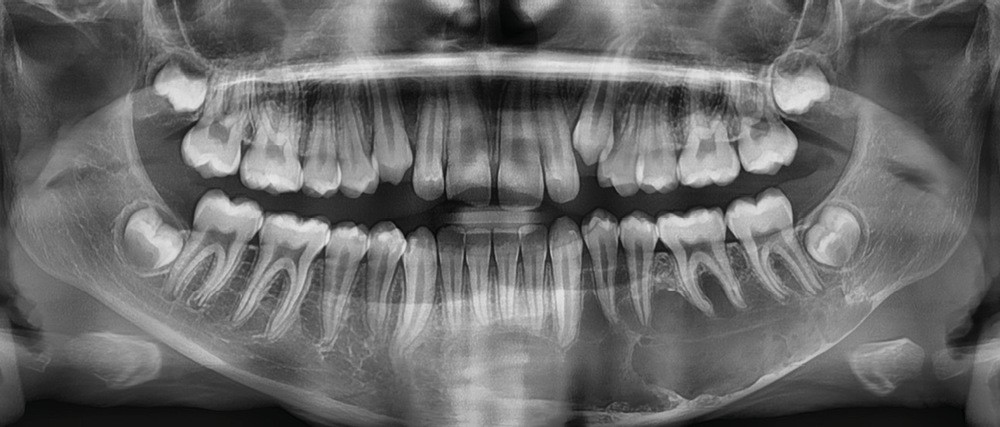

L’évolution clinique lente, la découverte fortuite et les examens radiologiques font évoquer un kyste essentiel (kyste osseux solitaire).

Il existe une zone ostéolytique unique, aux contours extrêmement fins, évidant la branche horizontale de la mandibule, et dont la limite supérieure est mieux marquée et dite « circinée », contournant les racines dentaires.